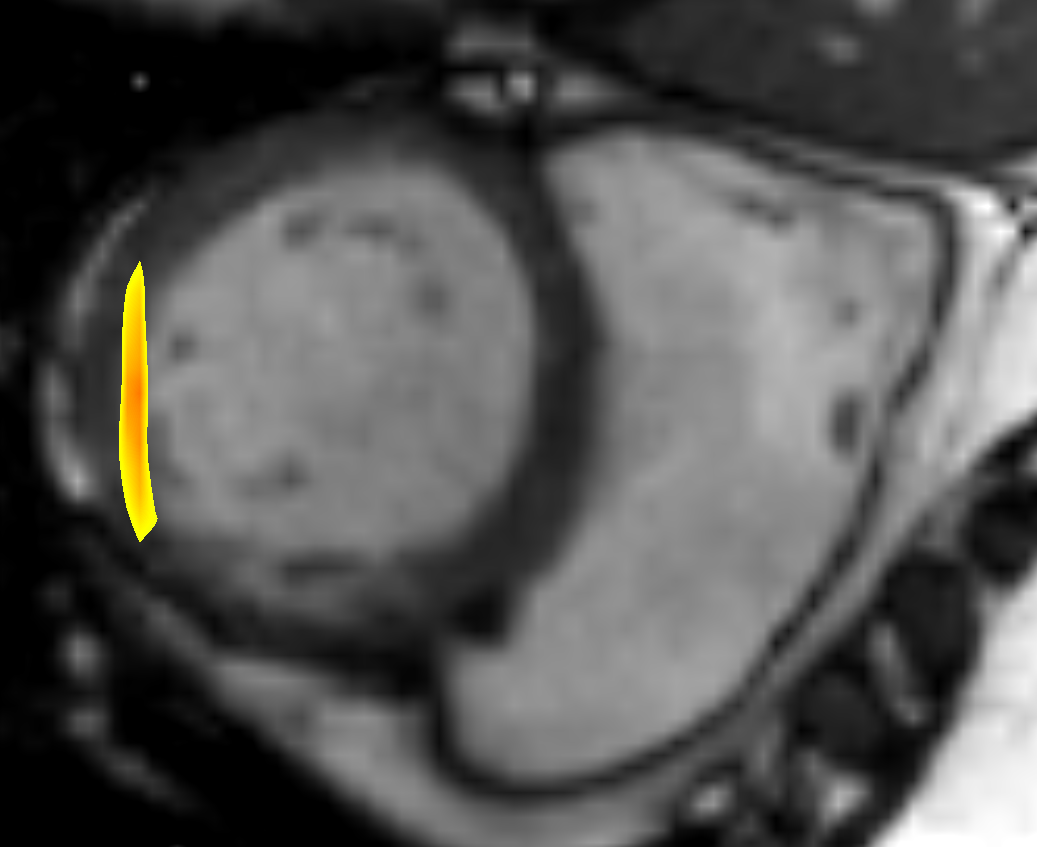

with V𝑉V being the set of all 3D voxel positions, N𝑁N the number of phase images, B𝐵B the set of voxel positions at the border of an image patch and P𝑃P the set of neighbouring voxel positions along a given axis. For a better understanding we visualised the sets B𝐵B and P𝑃P in Fig. 2. α𝛼\alpha controls the influence of the boundary smoothness constraint and d(x,y)𝑑𝑥𝑦d(x,y) calculates the Euclidean distance between positions x𝑥x and y𝑦y.

Refer to caption

Figure 2: The voxel sets needed for the calculation of the regularisation constraint R𝑅R are illustrated in this figure. The red line indicates a fictive image patch of 5 voxels. The area filled in blue represents the set of border voxels B𝐵B and the orange filled area P𝑃P contains the neighbouring voxels of the dark blue coloured voxel along the x-axis.